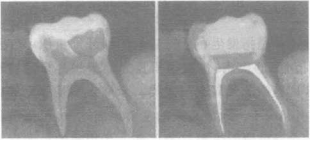

根管治療適用於被診斷為牙髓病或者根尖周病的患牙,使用專門的器械擴大成形牙根管,將存在於牙髓腔和根管內有炎症的牙髓組織和病原物全部清除,經過對根管的清理、成形、必要的藥物消毒及最後的嚴密充填,達到消除感染、堵塞和封閉根管空腔、防止再感染的目的。根管治療是一種較為複雜的牙髓治療方法,使用的器械多、步驟多,需要經過多個治療步驟和拍攝多張X線片才能完成整個過程。在治療期間和治療後一段時間,可能會出現疼痛等不適症狀,多數屬於正常反應,可按預約時間復診。如果疼痛嚴重、伴有局部腫脹和全身反應,應及時復診,酌情進一步治療。